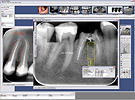

Digora Optima - Digitale Röntgeneinrichtung. Der Sinn des Gerätes ist, dass die Aufnahme anstatt auf einen Film auf eine strahlungsempfindliche Platte aufgezeichnet wird. Die Daten werden später durch ein Scanner eingelesen und auf dem Computer dargestellt. Seine Vorteile sind die Schnelligkeit, die wesentlich kleinere Strahlmenge (Zehntel im Vergleich zu dem Film), einfache Lagerfähigkeit, einfache und schnelle Aufarbeitung, detailiertes Bild, Planungsmodule usw.